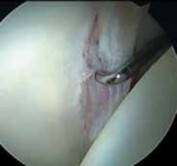

Labral repair is best suited for young patients when it is believed that simple débridement may result in inordinate sacrifice of healthy tissue ( TECH FIG 2).

1.

An optimal pattern is a tear at the articulolabral junction where a large segment of otherwise healthy tissue has been detached.

2.

Labral function is most dependent on its fluid seal.2 Thus, the goal of repair is to reapproximate the labrum to the adjacent acetabulum.

3.

The mechanical properties of the labrum are minimal; therefore, the recreation of a bolster effect such as that in the shoulder is not necessary.

A D E TECH FIG 2 • A. Sagittal MRA image demonstrates an anterior labral tear (

arrow

). B. Arthroscopy reveals a traumatic detachment of the anterior labrum (indicated by the probe). C. An anchor has been placed with suture limbs passed in a mattress fashion through the detached labrum. D. The labrum has been reapproximated to the articular edge. E. Viewing the peripheral aspect of the labrum, the suture is seen on its capsular surface, avoiding contact with the articular surface of the femoral head. (Courtesy of J. W. Thomas Byrd, MD.) ### TECHNIQUES